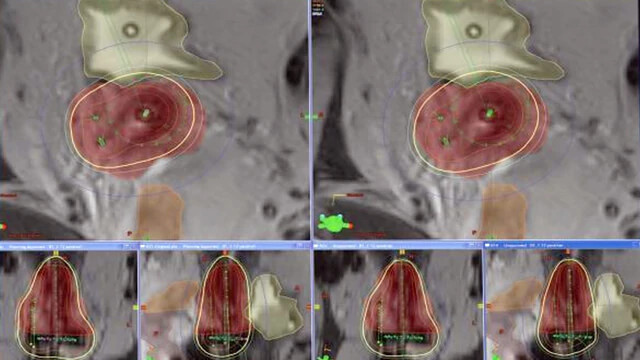

BrachyVision

Simplify complex treatment programs, giving you a comprehensive toolset that makes brachytherapy treatment planning efficient and consistent.